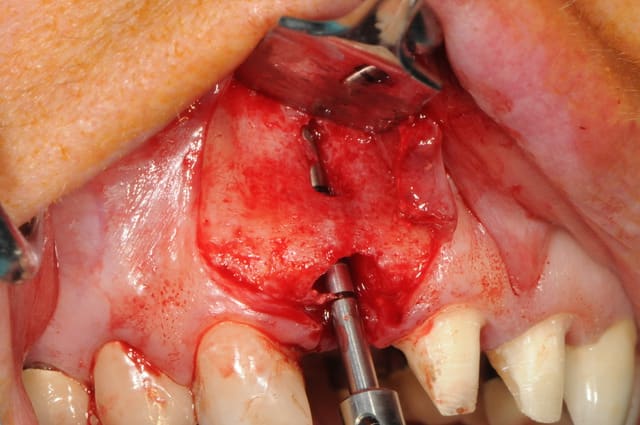

bon, je donne la réponse:

12 à 22 sont effectivement des couronnes:

-22 à été posée juste avant que je ne vois la patiente pour un problème récurent d'infection chronique sur 22.

je fais donc une résection apicale sur 22, mais manque de bol il y a récidive et le traitement échoue.

on décide donc d'extraire 22 tout en refaisant un bridge sur 11 et 21 avec un cantilever pour la 22 nouvellement extraite.

je dis à la patiente que la pose d'in implant n'est pas forcément ce qu'il y a de mieux et qu'il vaut mieux attendre la cicatrisation pour décider...